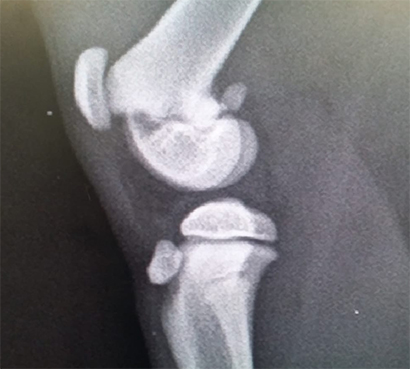

Dort wurde der junge Mann untersucht und es stellte sich heraus, dass der Sturz zwei schlimme Trümmerbrüche, einen im Vorder- und einen im Hinterbein, nach sich gezogen hatte.

++klick für groß++